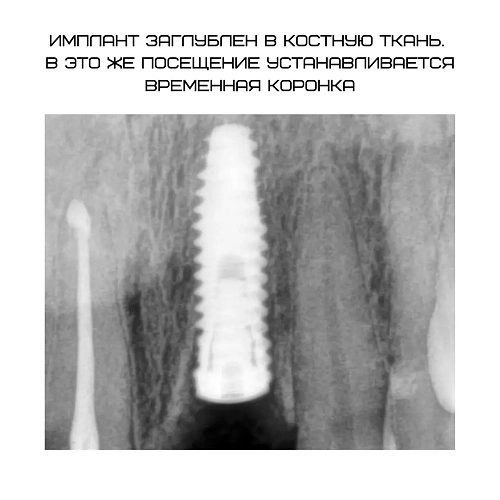

На фото пациенту проведена одномоментная имплантация